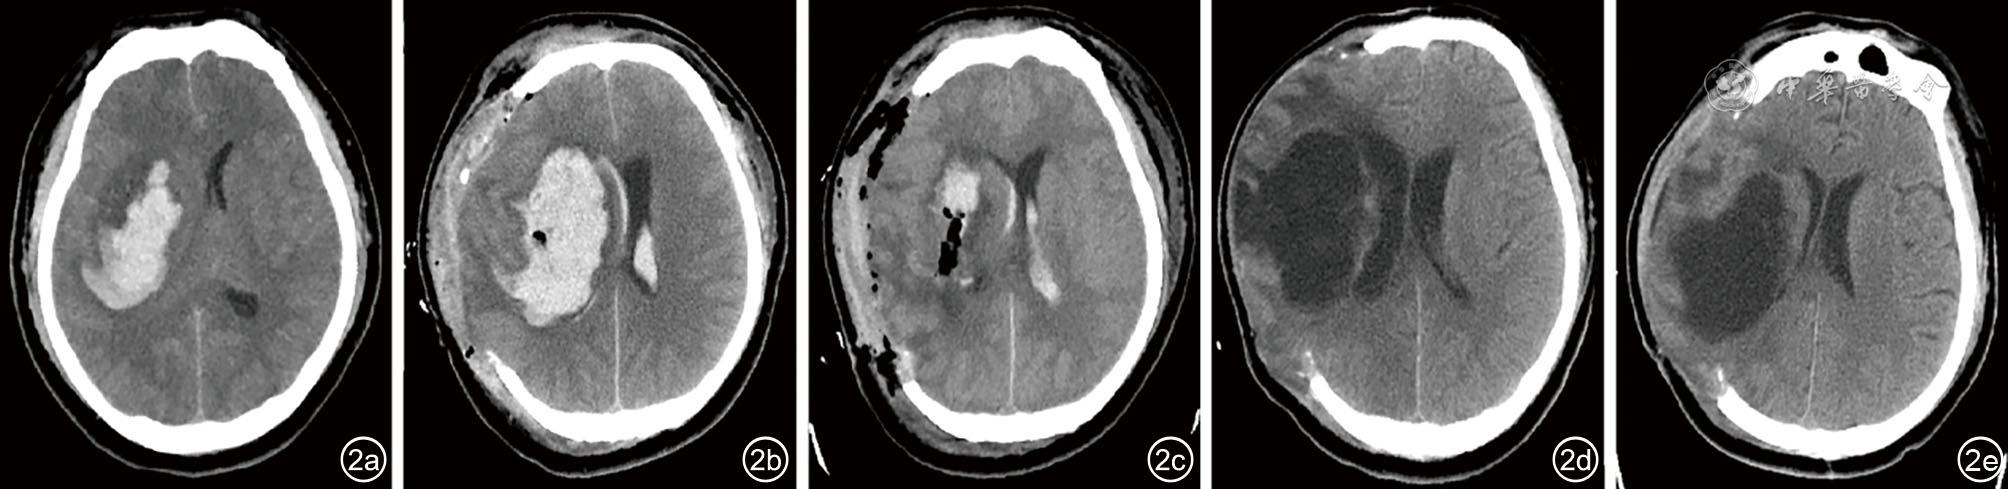

图2 病例2影像资料。图a:入院CT显示右基底节急性出血,中线左偏;图b:第1次开颅血肿清除术后CT显示右侧额叶、颞叶及基底节再出血、破入脑室,中线左偏;图c:第2次开颅血肿清除术后CT显示右基底节及脑室残余积血;图d:术后第13天CT显示位于右侧额顶颞岛叶及基底节的新发巨大囊肿,中线略右偏,脑室增大;图e:术后第20天CT显示囊肿引流后,脑室较前变窄。此时,患者的PSH症状已不再发作 注:PSH 为阵发性交感神经过度兴奋